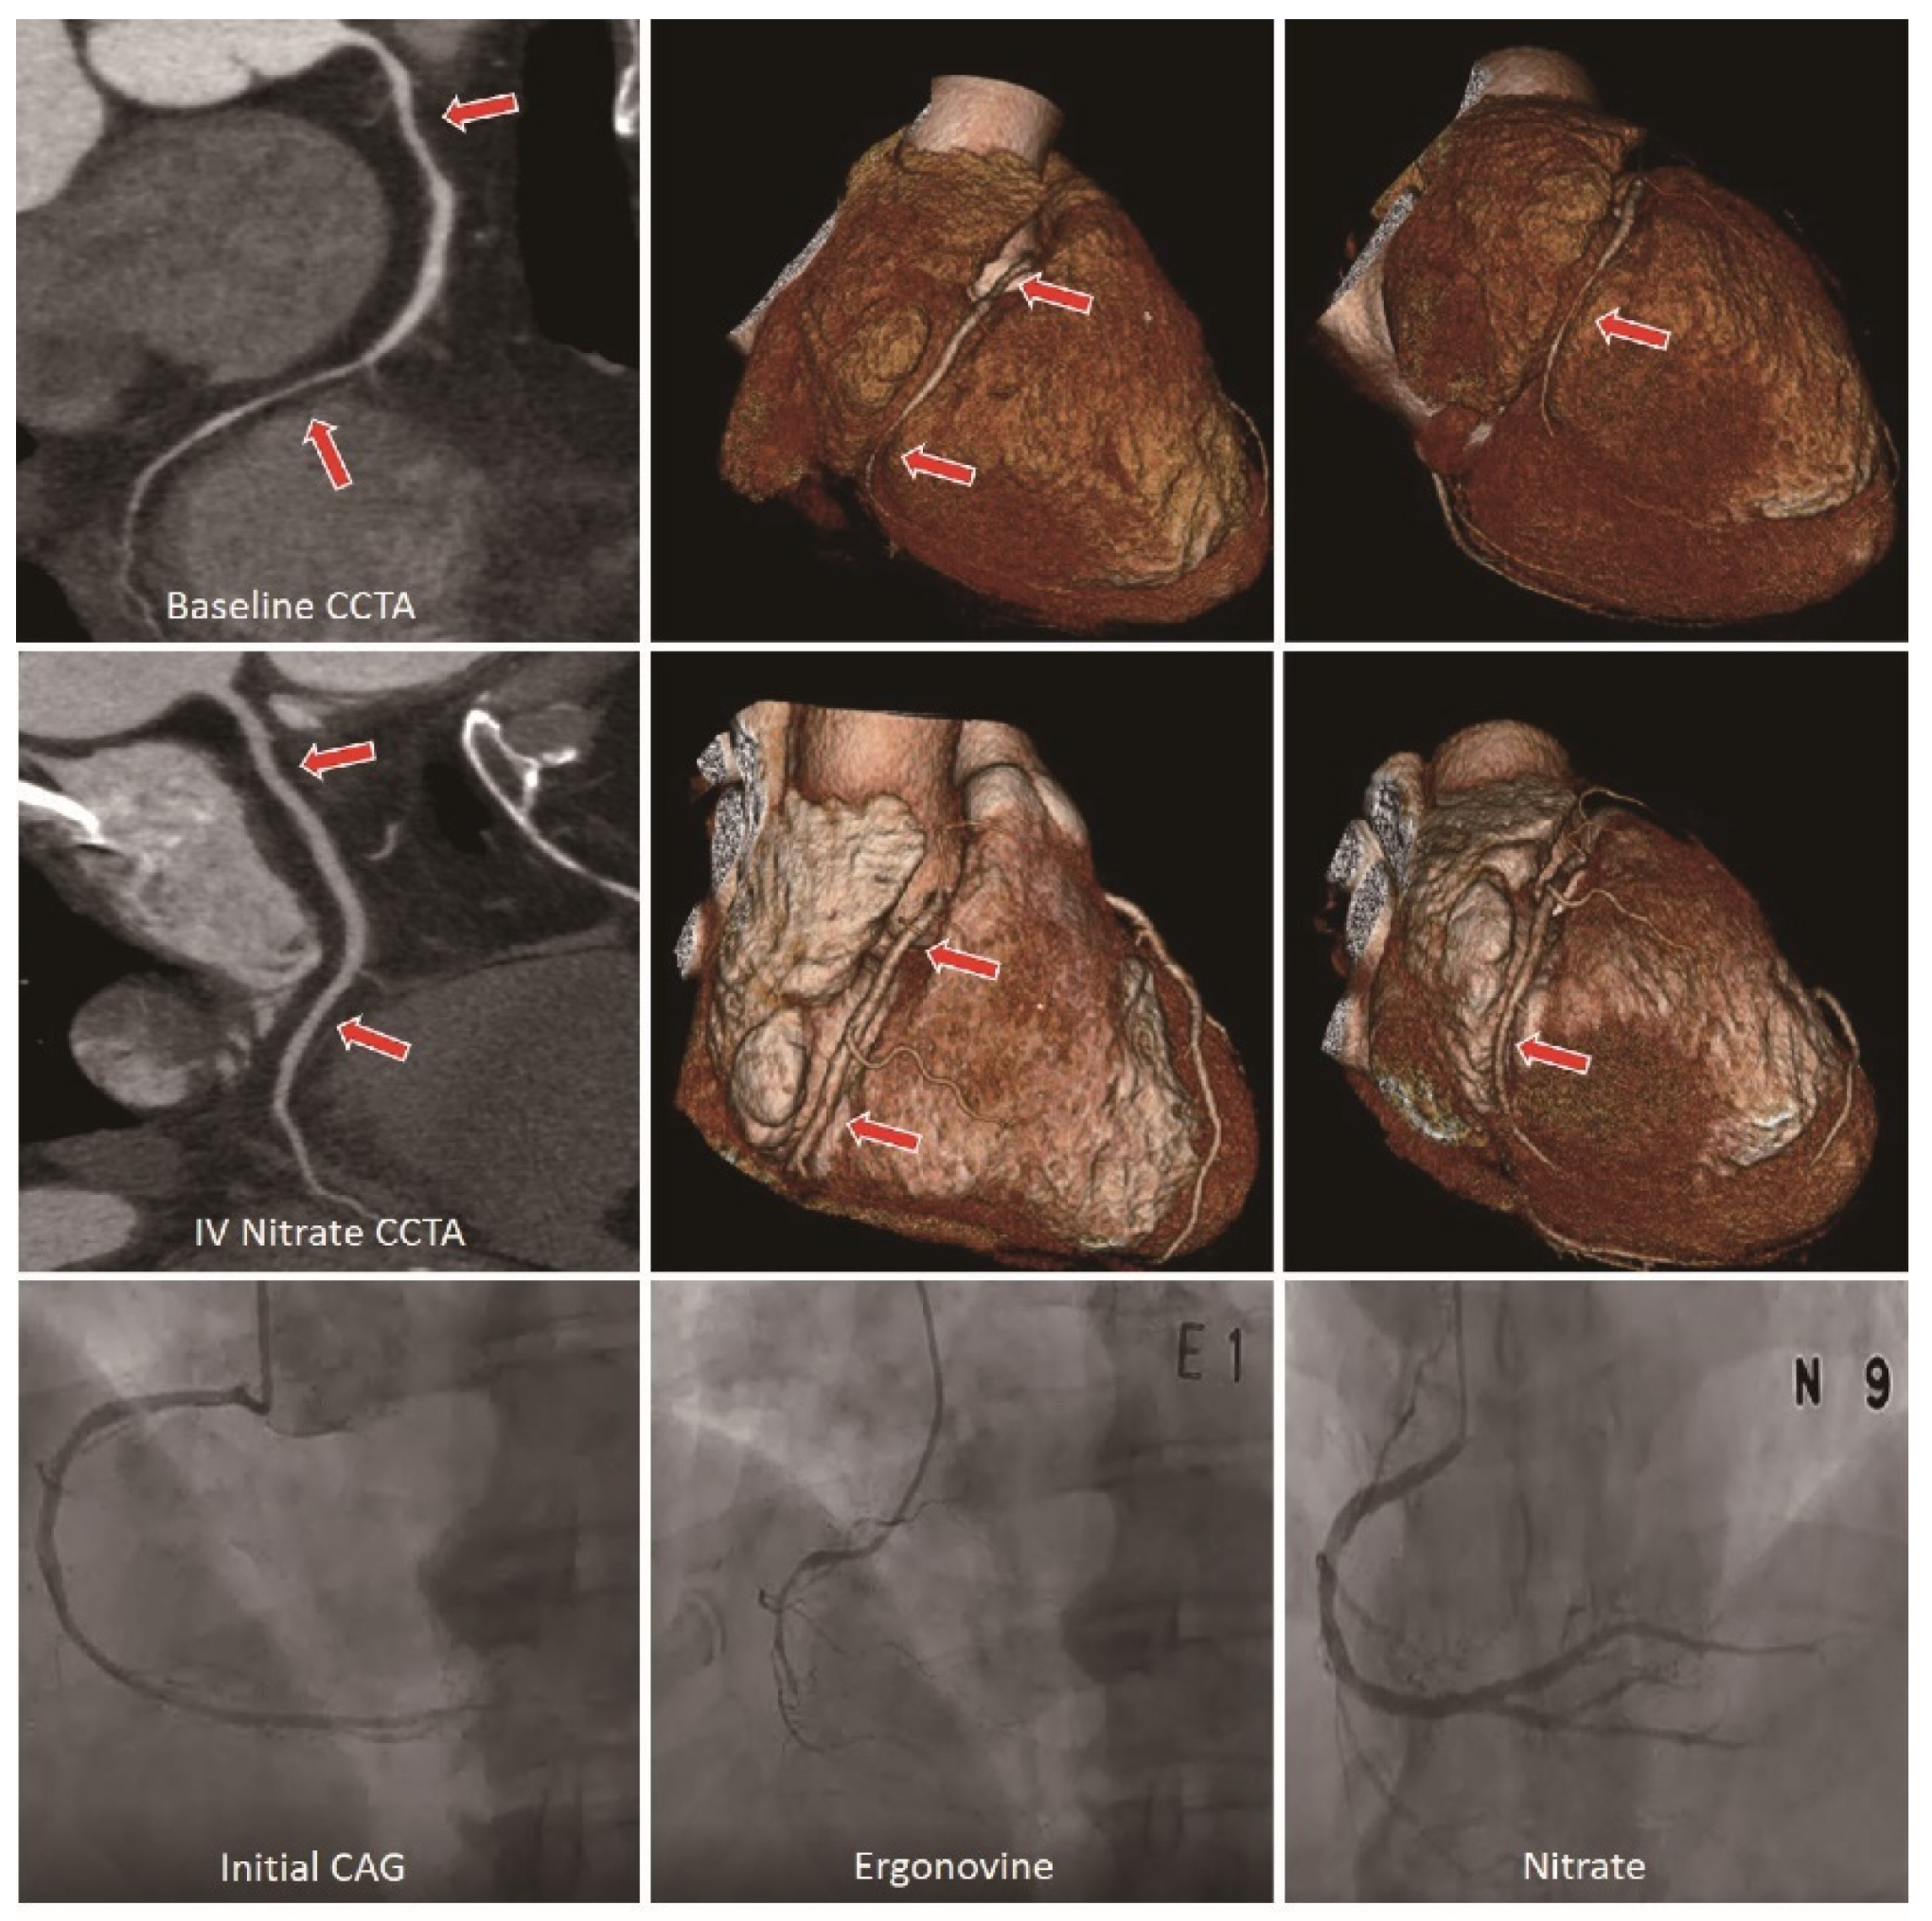

- Kang, E.J.; Kim, M.H.; De Jin, C.; Seo, J.; Kim, D.W.; Yoon, S.K.; Park, T.H.; Lee, K.N.; Choi, S.I.; Yoon, Y.E. Noninvasive detection of coronary vasospastic angina using a double-acquisition coronary CT angiography protocol in the presence and absence of an intravenous nitrate: A pilot study. Eur. Radiol. 2017, 27, 1136–1147. [Google Scholar] [CrossRef]

- Jin, C.; Kim, M.H.; Kang, E.J.; Cho, Y.R.; Park, T.H.; Lee, K.N.; Serebruany, V. Assessing Vessel Tone during Coronary Artery Spasm by Dual-Acquisition Multidetector Computed Tomography Angiography. Cardiology 2018, 139, 25–32. [Google Scholar] [CrossRef]

- Jin, C.D.; Kim, M.H.; Jo, S.J.; Lim, K. Severe multivessel coronary artery spasm detected by computed tomography: A case report. Eur. Heart J. Case Rep. 2020, 4, 1–5. [Google Scholar] [CrossRef]